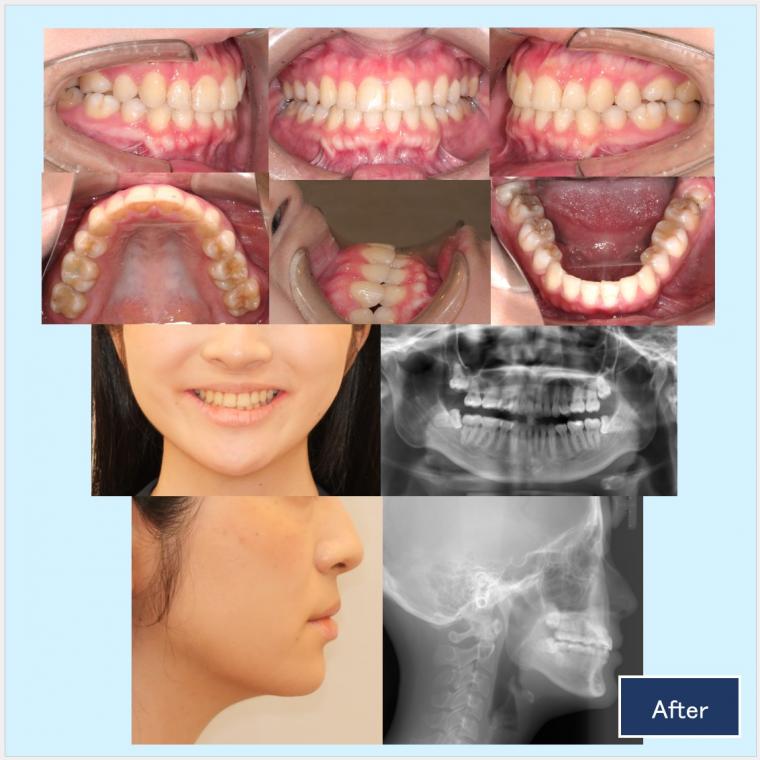

上顎両側5番、下顎両側4番を抜歯して、上下顎前歯部を後方移動致しました。

上顎左側臼歯部の頬側にもブラケット装置を装着し叢生の改善をしました。口元・側貌・スマイルライン共に美しい仕上がりになりました。

最終的な微調整では正中を出来る限り一致させる為に、顎間ゴムを使用して頂きました。

ご協力ありがとうございました。美しい口元、口腔内環境をこれからもぜひ維持していきましょう。

年齢:20代 治療期間:2年3ヵ月 治療回数:26回

◎ハーフリンガル:上顎 カスタムメイド型リンガルブラケット矯正装置(WIN)、セラミックラビアルブラケット矯正装置、下顎 プラスチックラビアルブラケット矯正装置

抜歯部位:上顎両側5番、下顎両側4番